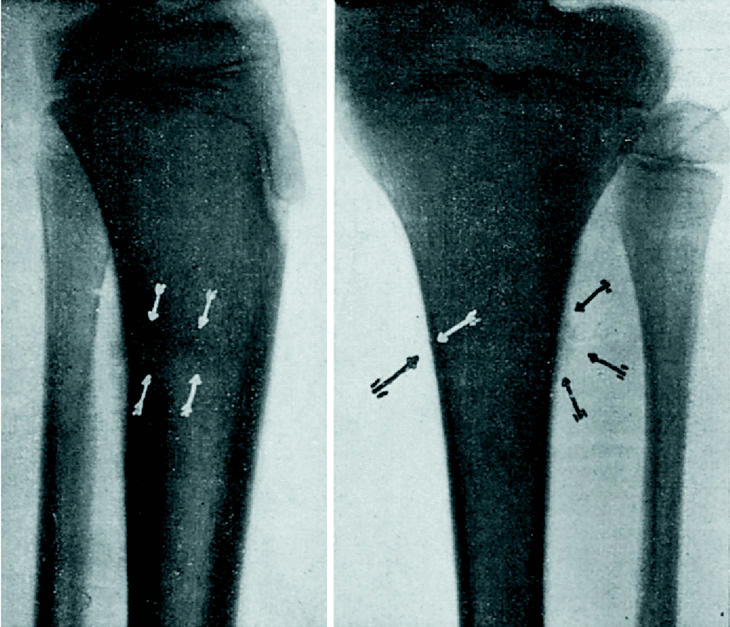

Radiografía anteroposterior (fig. 3): En el tercio superior de la tibia se observa lo siguiente: una fisura de la cortical en su parte interna, reacción perióstica de hueso osteoide en la parte externa, y uniendo ambos, una estrecha zona en la que el hueso parece adensado. Esta zona corresponde al límite entre metáfisis y diáfisis. Radiografía lateral (fig. 3): La cortical de la parte posterior está esfumada en un trayecto de uno y medio centímetros, con reacción perióstica evidente en el mismo punto. En el extremo superior de esta zona, que corresponde al límite entre la esponjosa y metafisaria y la compacta diafisaria, existe una zona transversal más densa que llega hasta el límite anterior del canal medular, sin afectar la cortical anterior.

Figura 3.

Diagnosticamos fractura lenta e incompleta de tibia, ya que un golpe directo hubiera lesionado más bien el borde anterior, que es normal en este caso. Como tratamiento, infiltraciones de novocaína al 1 por 100, sin adrenalina. después de la segunda inyección las molestias subjetivas han desaparecido.

El segundo caso, la simple sintomatología de tumefacción y dolor a la presión nos hace sospechar en una serie de afecciones circunscritas de típica localización en mitad superior de tibia; éstas son: osteomielitis crónica, tuberculosis, goma aislado y sarcoma. Pero el minucioso examen radiológico es el que nos da el diagnóstico. Ante todo, hay que evitar el error de tomar por una línea de fractura la línea epifisaria normal de la tuberosidad anterior de la tibia, que en este caso es bastante irregular (fig. 3). Hablan en pro de la fractura: 1.o, la presencia de la fisura cortical; 2.o, la existencia de la zona transvesal más obscura con la reacción perióstica del hueso osteoide; 3.o, la extensión transversal y no longitudinal del proceso.